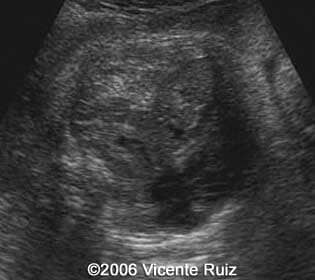

Axial views of the chest showing the left hemithorax occupied by an heterogeneous mass

Note the stomach into the left hemithorax

Note the absence of the stomach in the axial section of the abdomen